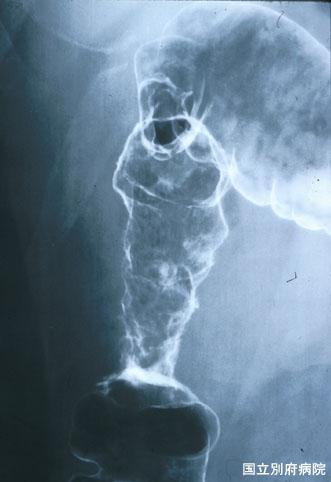

대장암과의 감별이 어려웠던 호산구증다증에 동반하는 허혈성 대방염(증례제시:국립 벳부병원)

염증성 및 궤양성질환/허혈성 장염(혈전증 포함)

대장/상행

X-P

40이상